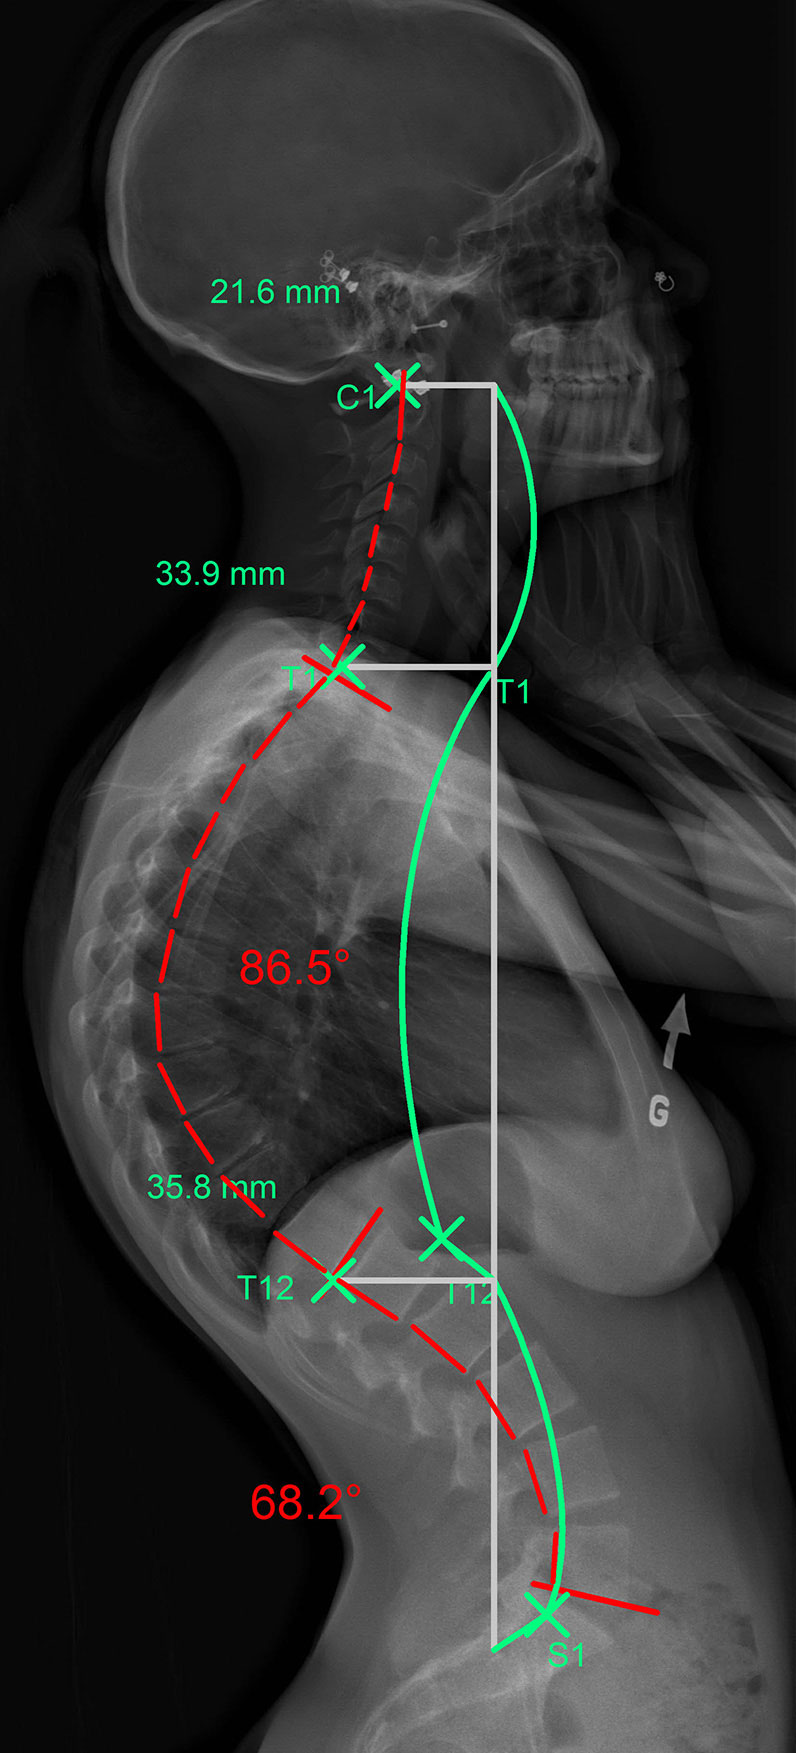

L’hypercyphose peut toucher de nombreuses parties de la colonne vertébrale thoracique. Sur les images suivantes, la ligne verte représente la courbe idéale que devrait avoir le patient. La ligne rouge représente, elle, la configuration anormale de sa cyphose.

La ligne verte représente la courbure idéale et la rouge celle que forme la colonne vertébrale du patient vue de profil.